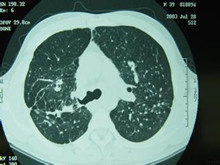

硅肺病是一种尘肺病,是一种严重的职业病。游离二氧化硅粉尘通过呼吸道在人体肺泡上积...

胸部CT